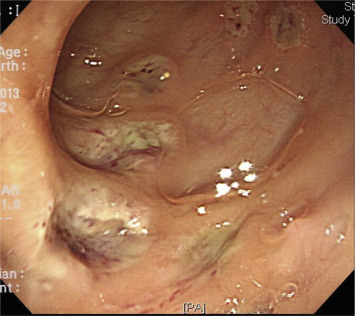

However, the patient continued to suffer from aggravating bloody diarrhea and abdominal fullness from July 2013. No body weight loss was noted during this period. Sigmoidoscopy revealed severe inflammation of the rectal mucosa and deep skip ulcerations with spontaneous bleeding (Fig. 2). He was referred to the emergency department of our hospital. On physical examination, pale mucosa and periumbilical abdominal tenderness were noted. The blood test results showed hemoglobin: 6.1 g/dL, WBC: 7.06 k/μL, Seg: 76%, Band: 16%, and platelet counts: 283 k/μL. The biochemistry test showed Alb: 3.1 g/dL, BUN: 25.3 mg/dl, Cre: 1.1 mg/dL, and CRP: 14.05 mg/dL. A stool sample showed 4+ occult blood and two to five pus cells/HPF. No protozoa or parasite ova were found in the stool. Empirical antibiotics with the third generation of cephalosporin, intravenous-form steroid [methylprednisolone 20 mg/day], and mesalamine were prescribed. However, bloody stool (>5 times/day), hypotension, and anuria developed. Stool tests, including protozoa, parasite ova, and bacterial cultures, all appeared negative. As hypoxemia progressed, intubation was performed. Hemodialysis was arranged, but the routine screening revealed anti-HIV antibody positive and western blot analysis confirmed the positive status of an HIV infection. The HIV viral load was 141,000 cp/mL. His hemogram showed WBC 14.32 k/μL, seg: 89.1%, Band: 8.9%, Meta: 1%, Lymph: 0%. The CD4 count was zero. A sudden onset of severe abdominal distension with peritoneal signs occurred, and a CT scan showed air in the rectum wall (Fig. 3), massive ascites, and free air in the abdomen (Fig. 4).

Figure 2. Colonoscopy image showing well-demarcated ulcerations in the sigmoid colon. |

We reviewed the patients previous data, endoscopic findings, and histological results. Neither typical, continuous, and confluent mucosal inflammation, ulcerations, granularity, nor loss of visible vascular pattern of the mucosa were present. The initial pathology report revealed the presence of ulcers with focal crypt abscesses, which were nonspecific features of colitis. Furthermore, when the slides were reviewed again, the initial biopsy revealed the presence of amebic trophozoites. Therefore, if the slides had been examined in more detail, the correct diagnosis may have been made earlier.